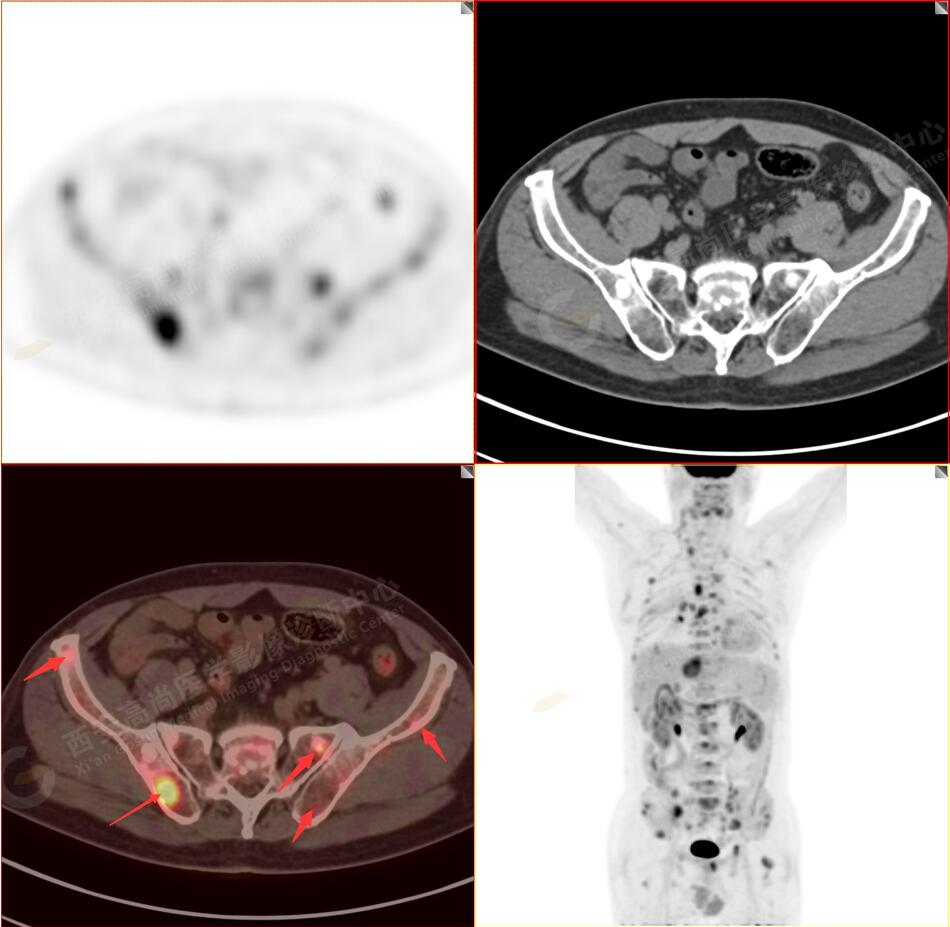

PET/CT圖像

2.以下為全身多發(fā)轉移灶

5.右側肱骨上段、左側肩胛骨、右側鎖骨胸骨端、胸骨、雙側多發(fā)肋骨、脊柱多發(fā)椎體及附件、雙側髂骨、雙側髖臼、雙側恥骨、雙側肱骨上段多發(fā)成骨性病變,呈不同程度FDG代謝異常增高,考慮為多發(fā)骨轉移瘤。